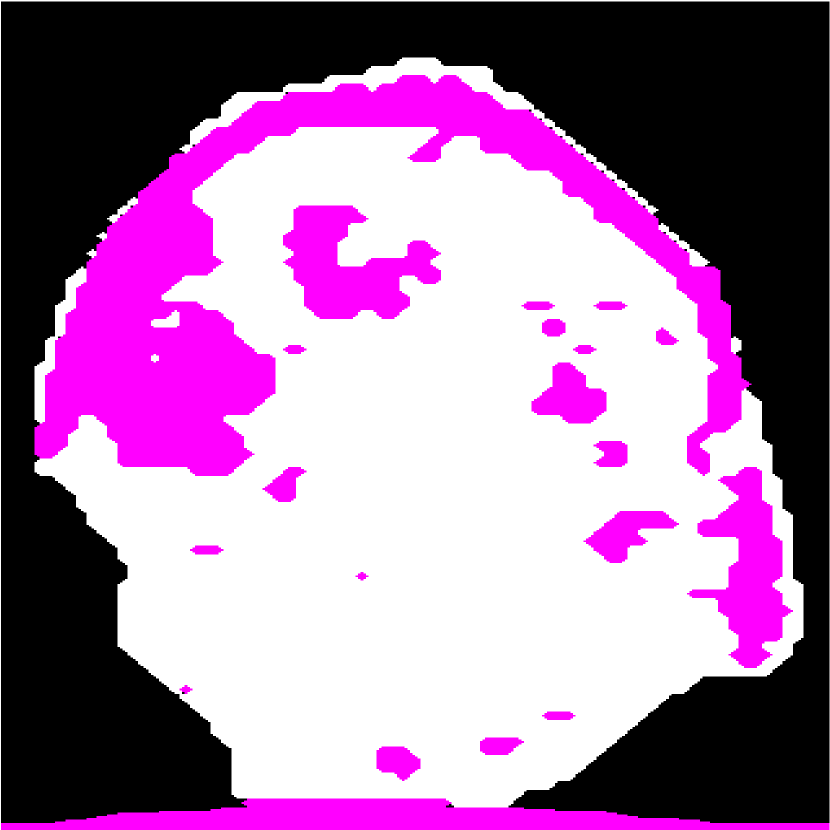

Figure 7: (a) The HFU image and the confident regions obtained by fusing results in the top rows of (b),(c), and (d). (b)(c)(d) Top row shows the segmentation results obtained by GC-LAE with different values of k𝑘k in the first round (no global energy). Bottom row shows the segmentation results obtained by GC-LAE in the second round with different k values (with global energy).

III-C1 Segment LNP and fat by GC-LAE

In the proposed framework, we apply GC-LAE in two rounds. In the first round, GC-LAE is applied with the local adaptive energy only. The top row in Figure 7 shows the segmentation results of GC-LAE obtained by several different k𝑘k in the first round. Because the contrast between LNP and the fat at left hand side (green arrow) is low, GC-LAE may segment some LNP voxels as the fat region when k𝑘k is small or segment all voxels as LNP when k𝑘k is high.

As demonstrated, there is not a single value for k𝑘k that will work well in all regions. Therefore we apply GC-LAE with several different k𝑘k values, and then fuse the results. The automatic selection of up to three k values is described in Sec. III-D. We use the intersection of the LNP regions obtained with different k𝑘k as the confident region for LNP (white region in Figure 7(a) bottom), and we use the intersection of the fat regions as the confident region for fat (pink region in Figure 7(a)). From these confident regions, we determine the mean and STD of LNP and the fat at different depths. To suppress the noise in the resulting mean and STD values, we further fit the mean and STD profiles along the depth into two separate spline functions using the spline-based approach with RANSAC [22].

In the second round, GC-LAE is applied with local adaptive-energy term and the global energy term (Eq. (2)). The global energy is defined by the depth-dependent profiles obtained from the confident regions in the first round. The bottom row of Figure 7 shows the segmentation results of GC-LAE with global energy which have more accurate boundary on the left. Similar to the first round of GC-LAE, we can fuse these results to obtain new confident regions for both LNP and fat, and derive the new depth-dependent mean and STD profiles.